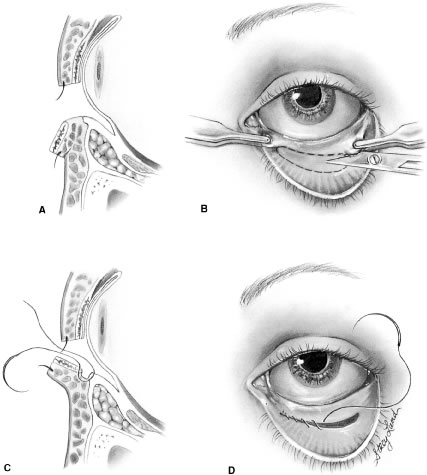

Ectropion and entropion share similar anatomic features. The most common predisposing anatomic factors for lower lid malpositions are horizontal eyelid laxity and weakness or defects of the lower lid retractors. The general weakness of the eyelid is caused by a weakness of the medial and lateral canthal tendons, permitting horizontal eyelid laxity.4 As such, it is best to consider lower eyelid laxity as resulting from laxity of the tarsoligamentous sling or support for the eyelid. The anatomic weakness can be demonstrated by the snap test. Downward retraction is exerted on the lower lid, pulling it away from the globe. On relapse, the lower lid should snap back against the globe spontaneously. Failure of the eyelid to snap back against the globe with a single blink indicates excessive laxity of the tarsoligamentous sling.

The lower eyelid retractors may be weakened or may actually become disinserted from the inferior tarsal border. Weakness or defect of the lower eyelid retractors creates in an instability of the inferior tarsal border that is manifested clinically as ectropion or entropion.

The development of ectropion and entropion is a reflection of the relationship between the anterior and the posterior lamellae. The eyelid position is maintained by an appropriate balance of the anterior and posterior lamellae. If tractional forces are unbalanced, eyelid malpositions may manifest as ectropion, entropion, or eyelid retraction. If traction is produced by the anterior lamella, either by chronic cicatricial changes or mechanical aberrations, the eyelid margin is everted away from the globe. This most commonly results from mild solar-induced changes or following surgical procedures or trauma of the eyelid, which produce a shortening or scarring of the skin and underlying orbicularis muscle.

Involutional entropion is more complex because of the multitude of factors producing this abnormality. The tarsal instability of entropic lids is due to horizontal eyelid laxity and loss of support of the lower eyelid retractors.10 The orbicularis muscle dynamics also assume a prominent pathophysiologic role in the production of entropion. In entropic eyelids, the preseptal orbicularis muscle overrides the pretarsal orbicularis muscle, which rolls the superior border of the tarsus internally. This is differentiated from spastic entropion, which is theoretically due to a spasm of Riolan's muscle. However, the primary differentiating feature of spastic entropion is a specific precipitating etiologic factor, such as recent eye surgery, eyelid edema, or ocular inflammation with secondary eyelid edema. An appreciation of the multiple etiologic causes of entropion has resulted in the evolution of combined approaches to correcting the various anatomic abnormalities and stabilizing the tarsus and orbicularis muscle.11–14